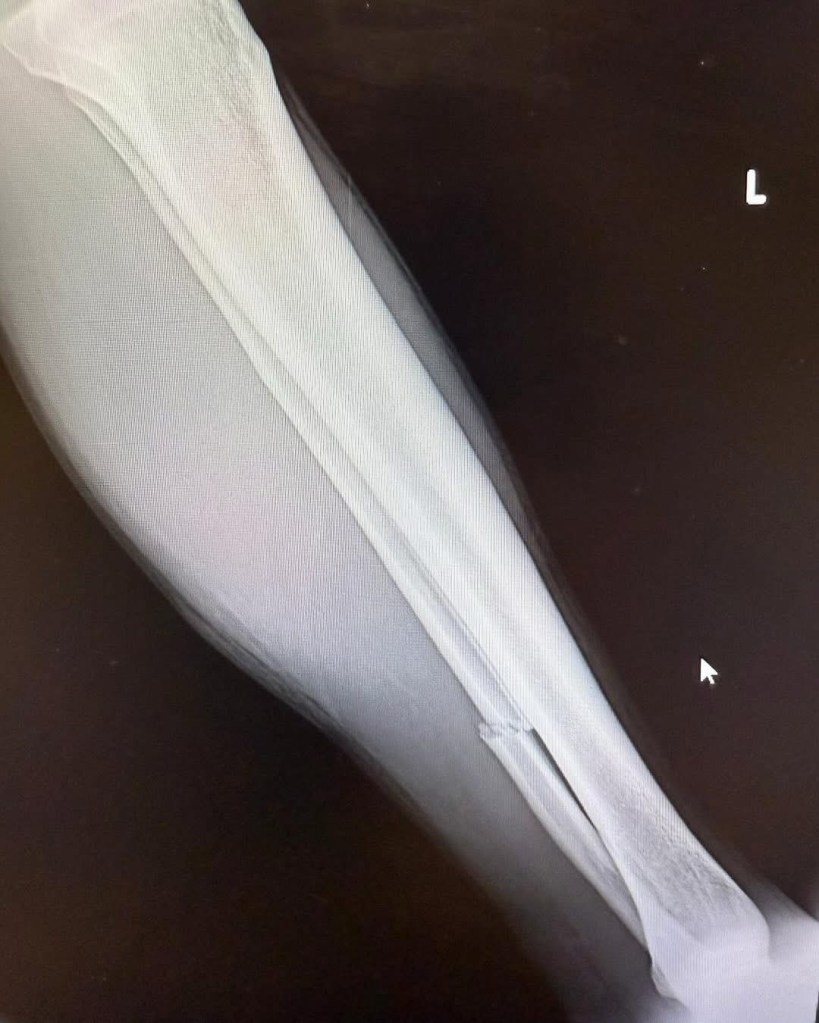

The true extent of the injury was only discovered after further medical evaluation following the weekend’s racing. The fibula, the smaller of the two bones in the lower leg, was confirmed broken, forcing Tomac to withdraw from upcoming rounds starting with this weekend’s event in Detroit.